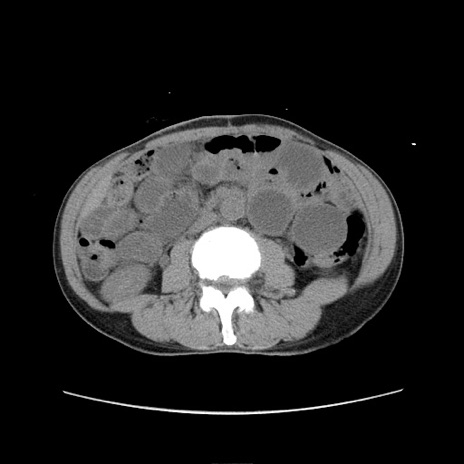

症例11(横断像)

【症例】 60歳代男性

【主訴】 下腹部痛

【現病歴】 本日夜中より下腹部痛の症状認め、受診。

【既往歴】 膀胱癌(膀胱全摘+尿管皮膚瘻術) 、胃癌術後

【身体所見】 BT 35.3℃、PR 58/min、BP 136/98mHg、腹部平坦、軟、腸蠕動音±、ストマ留置あり、左上腹部~正中部に圧痛あり、反跳痛なし。

【データ】WBC 5100、CRP0.01